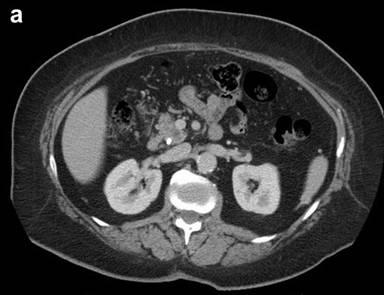

Physical exam was unremarkable aside from jaundice. Laboratory investigations revealed elevated bilirubin at 160 μmol/L (reference range: 0-20 μmol/L) and moderately elevated transaminases. ERCP revealed abnormal papilla with a red, yellow mass protruding through the papillary orifice. The head and body portions of the main pancreatic duct were dilated as were both the common bile duct and intrahepatic bile ducts. An abrupt cutoff was noted in the distal common bile duct, suggesting a mass in the biliary tree. A biliary stent was therefore inserted to maintain patency. Biopsies obtained at the time revealed large atypical cells indicative of malignancy. A repeat CT showed a 2.0 cm mass in the uncinate process, without evidence of local or distant metastases (Figure 1ab). The patient underwent a standard pancreaticoduodenectomy. A mass within the uncinate process was easily palpated. Superior mesenteric vessels were not involved by tumor. No evidence of distant metastases was noted. The patient remained stable throughout the operation and postoperatively the patient recovered without complications. She was discharged from hospital on post-operative day 8.

Figure 1. Computed tomography: coronal (a.) and sagital (b.) views of the mass. |